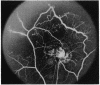

In a prospective study of 38 patients, who were initially selected as being at an early stage of sickling retinopathy, three developed circular black chorio-retinal scars (black sunbursts) during a period of 6 to 24 months. These lesions appear to be the sequelae of intraretinal and subretinal haemorrhage. They occur in the fundus periphery and do not interfere with vision.